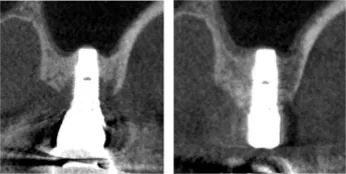

Dr.Tachikawa_Fig.6

Fig. 6. Comparison of X-ray CT image at the onset of peri-implantitis and approximately half year after regenerative treatment (coronal image).